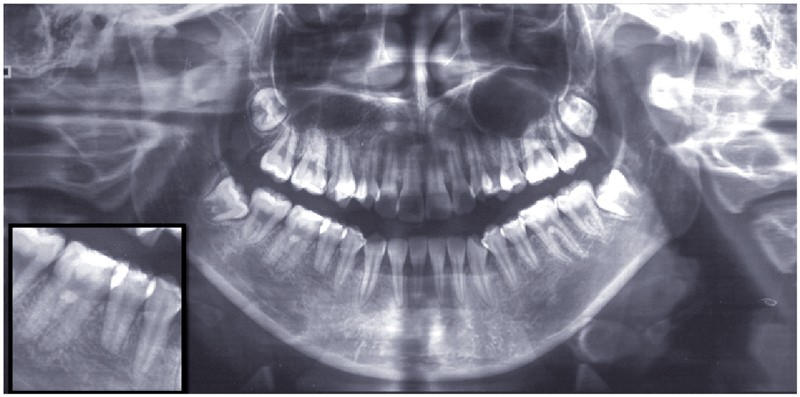

Diagnostic (fig. 1 à 3)

Sylvie se présente à l’âge de 15 ans avec une classe III squelettique (ANB -7,6°) d’origine maxillaire et mandibulaire sur un schéma facial à tendance hyperdivergent (FMA 31°) (fig. 1).

La classe III d’Angle et l’occlusion inversée s’accompagnent de signes de compensations alvéolo-dentaires : vestibuloversion des incisives supérieures (I/SN 114°) et linguoversion des incisives inférieures (IMPA 86°). L’encombrement à l’arcade maxillaire est important, souligné par des canines en infra-mésio-vestibulo-position.

Le choix du plan de traitement s’est porté sur un traitement chirurgico-orthodontique avec réalisation d’une classe II thérapeutique afin de limiter les déplacements dentaires à l’arcade mandibulaire suite au dépistage de rhizalyses idiopathiques sur les prémolaires inférieures (fig. 3) et de l’absence d’encombrement.